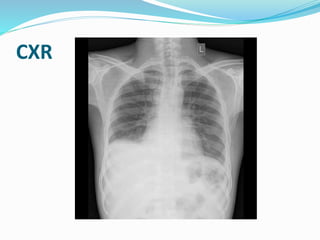

CXR

Chest X ray

 Pulmonary venous congestion and pleural effusions (late in

the disease).

 Calcified pericardium is highly suggestive of CP when present

in a patient with constrictive/restrictive physiology.

 Chest Radiography

 Findings are commonly unremarkable.

 Severe pericardial calcification (20-30%).

 If no significant pericardial effusion - cardiac silhouette may

appear normal.

 The superior vena cava may be dilated.

 Pleural effusions are common (late), usually bilateral.